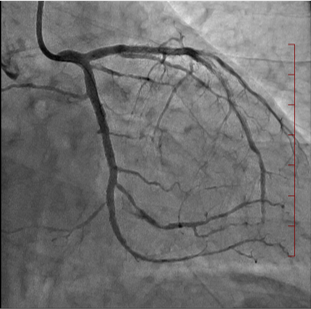

経皮的冠動脈形成術

経皮的冠動脈形成術とは、狭くなった、あるいは詰まった冠動脈(心臓の筋肉に血流を送る血管) に対し、カテーテルを用いる治療法の総称です。バルーンやステントを使用して冠動脈を広げる治療です。

| 治療前 | ステント留置中 | 治療後 |